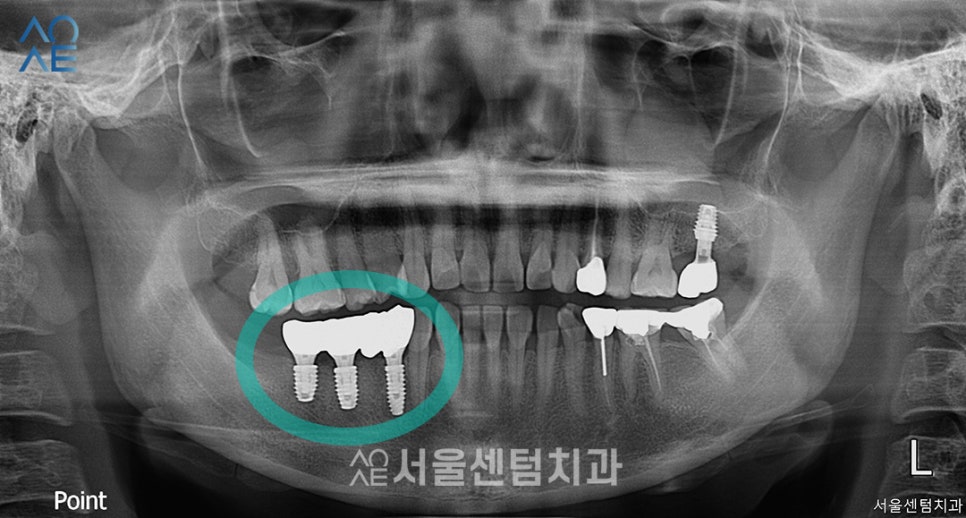

픽스처가 잇몸뼈와 잘 융합되었고

이 날은 이제 경과가 괜찮다고 판단되어

보철물 제작을 위한 인상채득을 진행하였습니다.

보철물까지 장착 완료한 모습입니다.

총 3개를 식립하긴 하였지만

브릿지 형태로 수복하여서

치아의 기능과 심미성을

올바르게 회복할 수 있게 해드렸습니다.

안정적인 방향으로 잘 식립되었고

뼈이식도 성공적으로 잘 되었습니다.